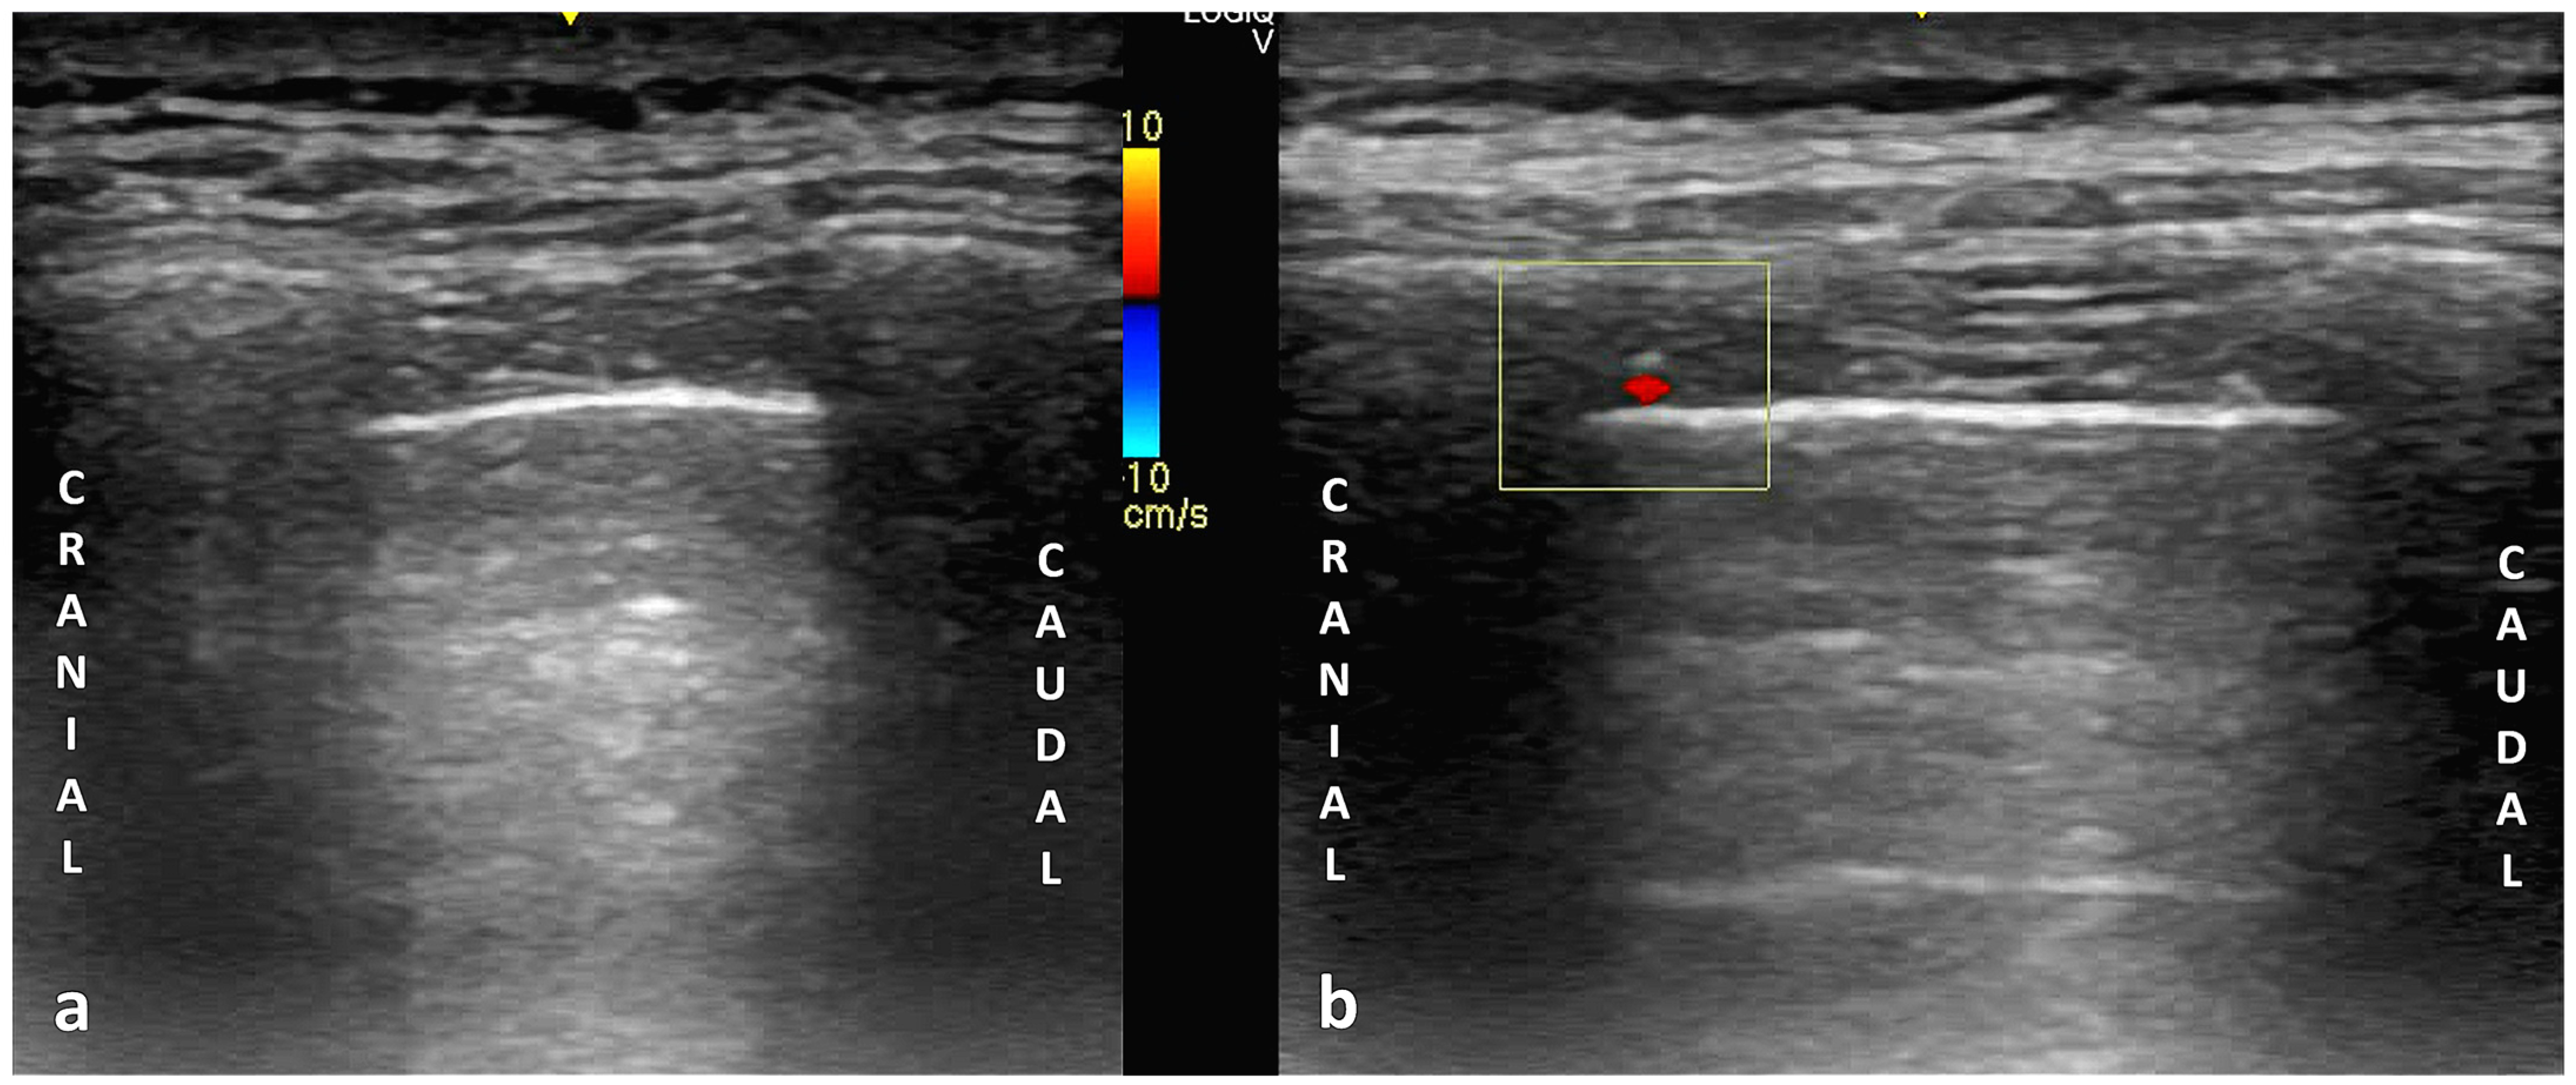

6. Principles and Techniques of Color Doppler Thoracic Ultrasound Imaging

6.1. Principles of Color Doppler Imaging in Thoracic Ultrasound

6.2. Technical Parameters in Ultrasonography: Probe Selection, Machine Configuration, and Scanning Techniques